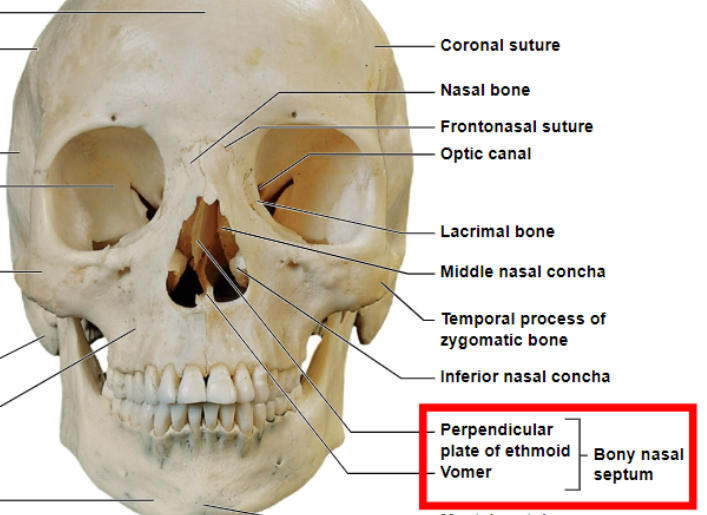

perpendicular plate of ethmoid and the vomer

what makes up the bony nasal septum